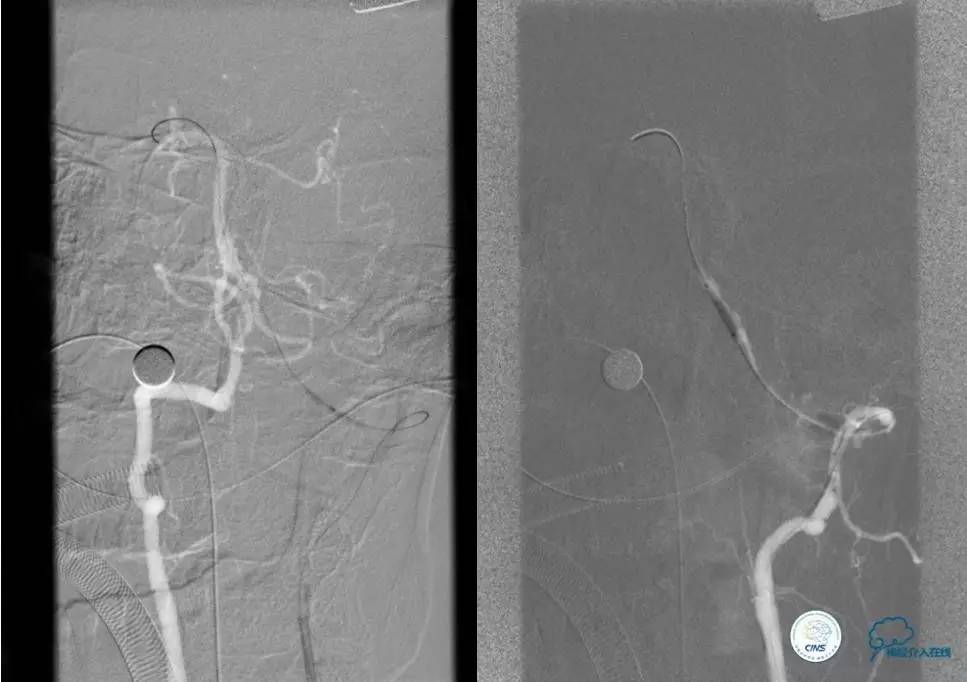

▼术前DSA

▼术中DSA

▼术后DSA